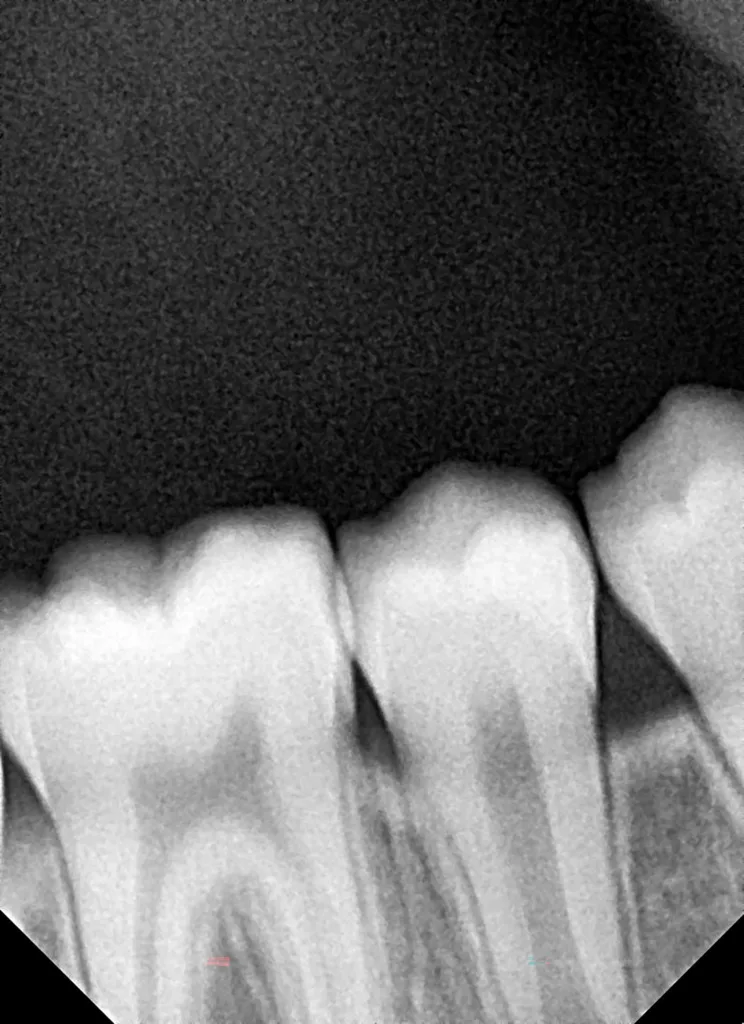

Im Rahmen der jährlichen Kontrolluntersuchung wurde bei einem achtjährigen Mädchen auf der routinemäßig angefertigten Röntgenaufnahme eine mittelgroße PEIR des Zahnes 46 (Grad 2 der Läsion nach Seow) entdeckt (Abb. 43). Die Patientin war komplett beschwerdefrei und der Zahnschmelz des betroffenen Zahnes sah intakt aus (Abb. 44 und 45). Weil auch hier der PEIR-Defekt gräulich durchschimmerte (Abb. 44 und 45) und der Zahn bereits seit einem Jahr durchgebrochen war, entschieden wir uns in diesem Fall, den Defekt klassisch mit Komposit zu restaurieren. Unter Lokalanästhesie mit Septanest 1/100 000 (Septodont, Frankreich) wurde zunächst Kofferdam mithilfe der Klammer U67 (KSK Dentech, Japan) gelegt (Abb. 45). Weder visuell noch mittels Sondierung konnte eine Verbindung zur Läsion festgestellt werden. Deswegen wurde an der Stelle, an welcher der PEIR-Defekt gräulich schimmerte, intakter Zahnschmelz der lingualen Querfissur entfernt (Abb. 46). Innerhalb der Läsion wurde nekrotisches intrakoronales Weichgewebe vorgefunden (Abb. 47), das problemlos mittels RONDOflex plus 360 (KaVo Dental, Deutschland) mit dem 27-µm-Pulver vollständig entfernt werden konnte. Der Boden des Defektes zeigte eine glatte, runde Form sowie helles, hartes und intaktes Dentin. Eine Präparation war nicht erforderlich, es wurde lediglich die Zahnschmelzkante geglättet (Abb. 48). Für die Restauration kamen erneut das Adhäsiv Optibond FL (Kerr, USA) und das Komposit Estelite ASTERIA OCE, A2B und Universal Flow AO2 (Tokuyama, Japan) zur Anwendung (Abb. 49). 6 Monate nach der Behandlung zeigte sich das Ergebnis sowohl aus klinischer als auch radiologischer Sicht stabil wie die Abbildungen 50 und 51 zeigen.

Das fünfjährige Mädchen stellte sich 2017 zur jährlichen Routinekontrolle vor. Im Rahmen der Untersuchung wurden Röntgenaufnahmen der Milchmolaren gemacht (Abb. 2). Der klinische und radiologische Befund der vor uns früher gelegten Kompositfüllungen war gut, es wurde allerdings eine PEIR an den noch nicht durchgebrochenen ersten bleibenden Molaren festgestellt (Abb. 2). Den Eltern wurde empfohlen, sich unverzüglich bei Beginn des Durchbruchs der ersten Molaren erneut zur Behandlung vorzustellen. Ein Jahr später erschien die junge Patientin schmerzfrei zur Kontrolle. Der Zahn 36 war noch teilweise mit Gingiva bedeckt. Auf einer neuen Röntgenaufnahme (Abb. 1) wurde die PEIR-Läsion mit unveränderter Größe in pulpanahen Bereichen bestätigt (Grad 3 der Läsion nach Seow). Der Zahnschmelz sah intakt aus, es konnte kein pathologischer periapikaler Befund bei den noch nicht ausgewachsenen Zahnwurzeln festgestellt werden. Daraufhin wurden die verschiedenen Behandlungsmöglichkeiten von Fissurenversiegelung bis Vitalerhaltung der Zahnpulpa mit den Eltern des Kindes besprochen.